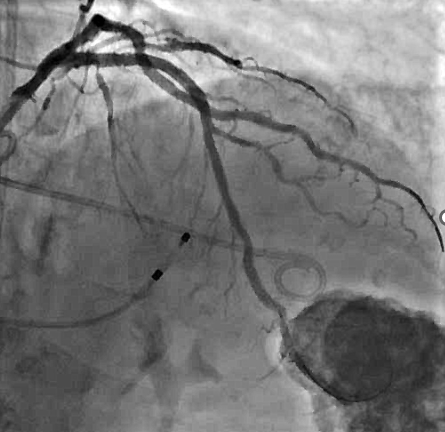

冠脉造影及介入治疗:将ACIST CVi血管造影注射系统调整至冠脉造影模式,完善冠脉造影。结果示:LM未见明显狭窄,LAD近端80%狭窄,严重钙化,IVUS可见360°钙化。回旋支少量斑块浸润,右冠状动脉30-40%狭窄。决定处理LAD,由于患者存在严重钙化,使用Shockwave球囊预处理打开钙化,后植入3.0*24mm +3.5*24mm药物涂层支架,效果满意。